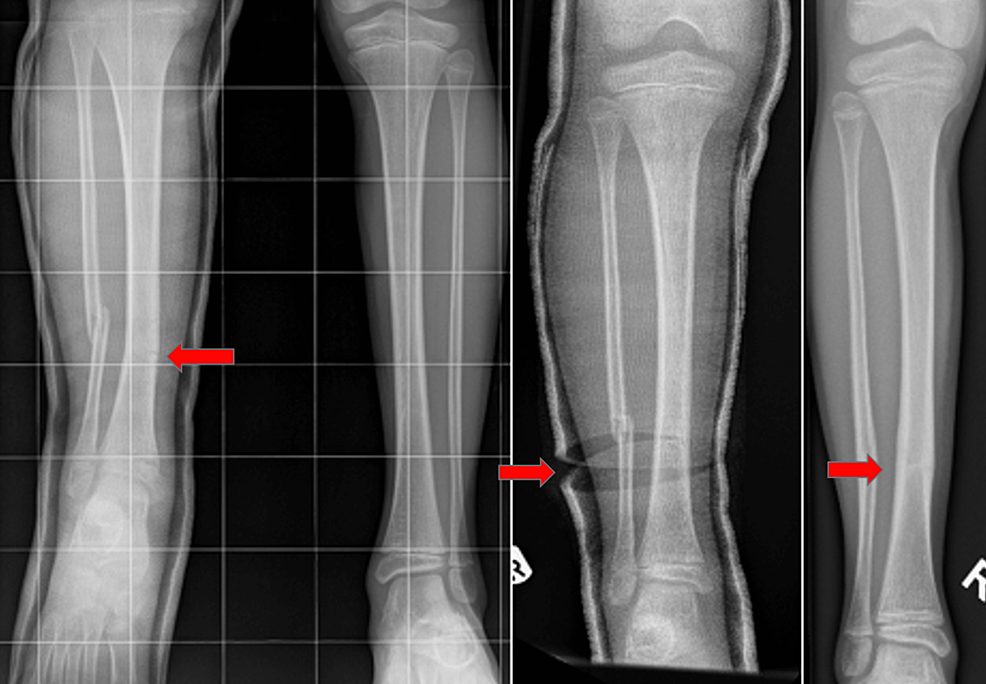

Figure 1 from Wedge Tibial Shaft Fractures Treated with Interlocking IM Tibia Wedge Fracture Diaphyseal tibial fractures are the most common long bone fracture. proximal third tibia fractures are relatively common fractures of the proximal tibial shaft that are associated with high rates of soft tissue. fracture dislocations (l) are caused by rotational movement and shearing. It typically takes a major force to cause this type of broken leg. a tibial. Tibia Wedge Fracture.

Tibia and fibula, shaft wedge fracture, spiral wedge—42B1 Tibia Wedge Fracture proximal third tibia fractures are relatively common fractures of the proximal tibial shaft that are associated with high rates of soft tissue. Diaphyseal tibial fractures are the most common long bone fracture. fracture dislocations (l) are caused by rotational movement and shearing. It typically takes a major force to cause this type of broken leg. Currently available tibial. Tibia Wedge Fracture.